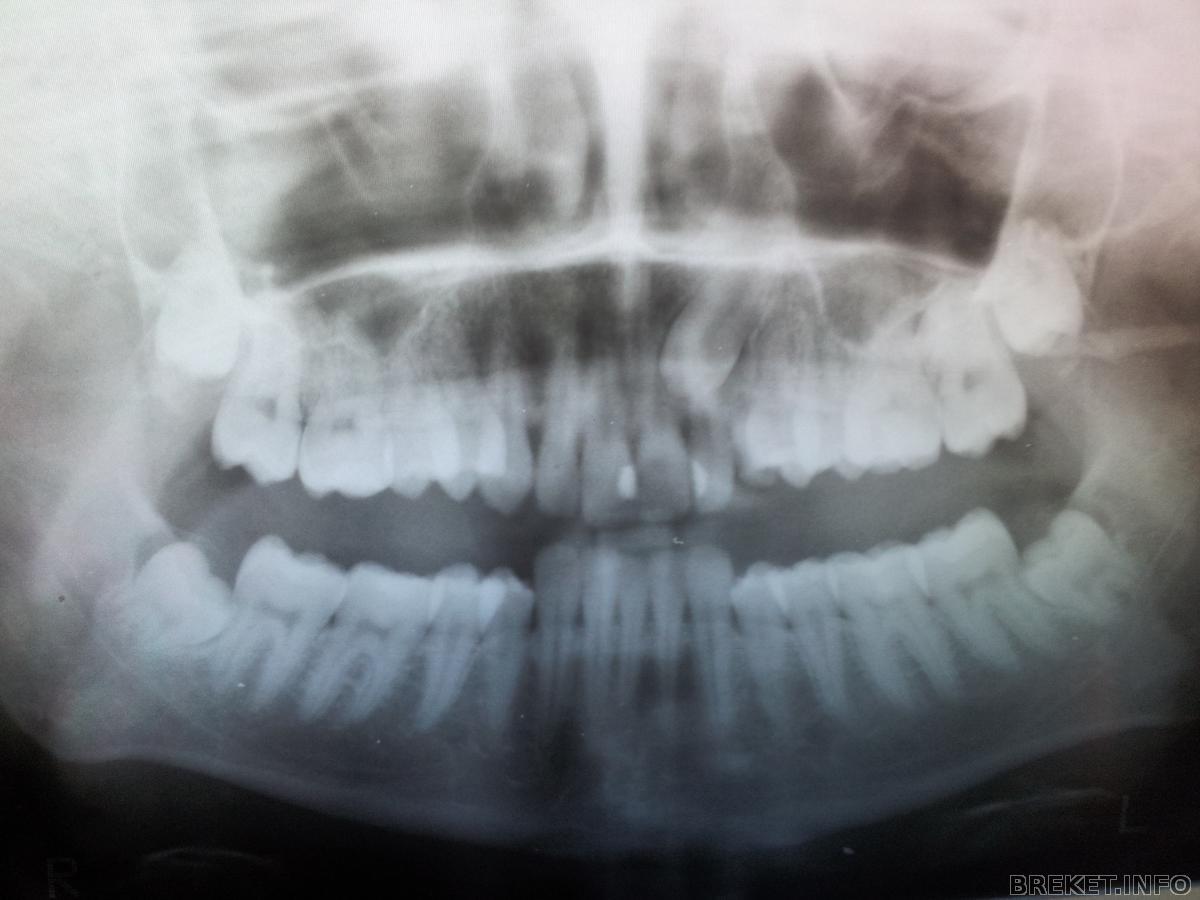

Снимки моего клыка.

Да, лежит он очень высоко, но зато хорошо лежит)